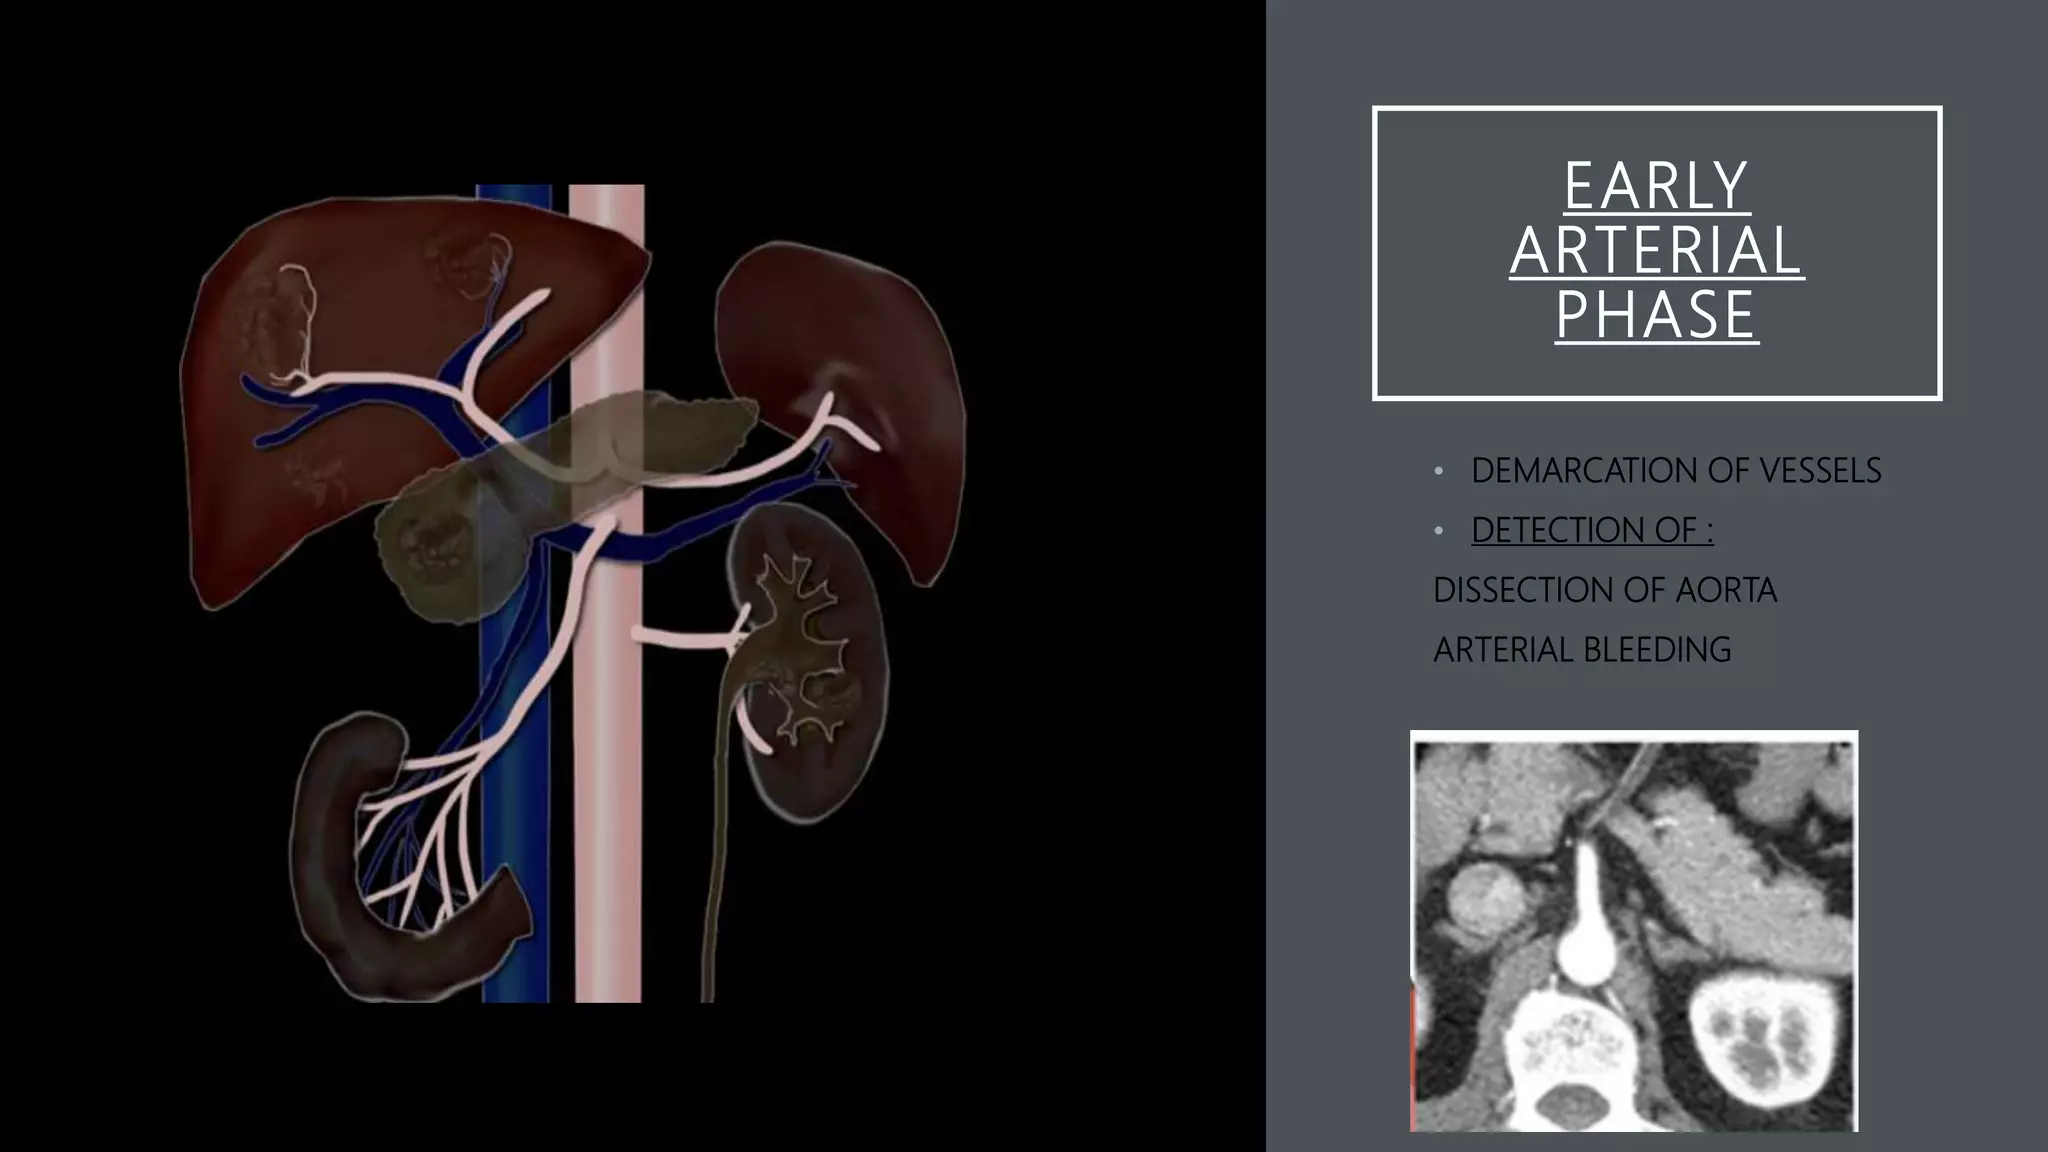

EARLY

ARTERIAL

PHASE

• DEMARCATION OF VESSELS

• DETECTION OF :

DISSECTION OF AORTA

ARTERIAL BLEEDING

EARLY ARTERIAL PHASE • DEMARCATION OFVESSELS • DETECTION OF : DISSECTION OF AORTA ARTERIAL BLEEDING